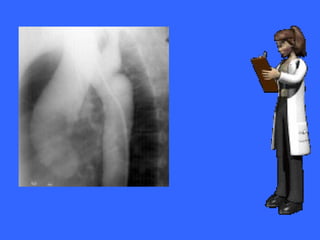

Marcada cardiomegalia, hipertensión pulmonar

Marcada cardiomegalia e incremento del flujo pulmonar